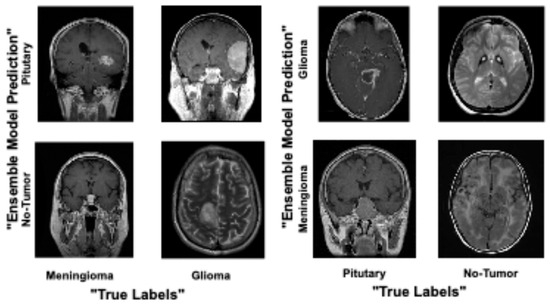

4. Results and Analysis